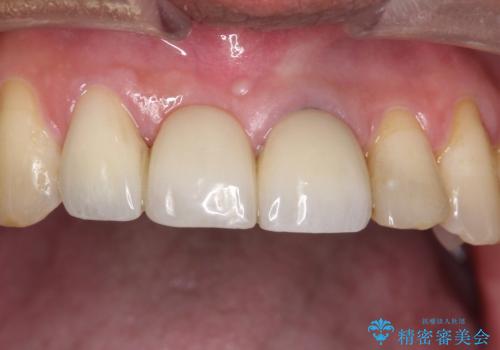

- 矯正治療終了後の患者様です。

前歯が欠損しており、ブリッジでの修復を希望されましたので、オールセラミッククラウン(スタンダード)で治療を行いました。

より審美的に色調や形態をこだわりたい場合はオールセラミッククラウンのスペシャルやエクセレントにグレードを上げていただくことで可能です。